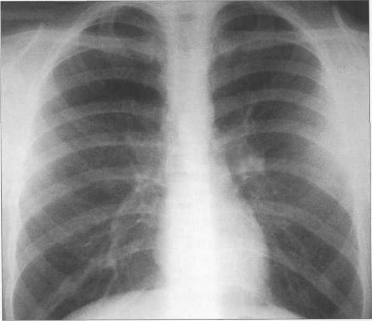

РЕНТГЕНОГРАММА НОРМАЛЬНОЙ ГРУДНОЙ КЛЕТКИ В ПЕРЕДНЕМ ПОЛОЖЕНИИ.

1 — дуга левого желудочка; 2 — дуга восходящей аорты; 3 — дуга правого предсердия; 4 — дуга ушка левого предсердия; 5 — дуга легочной артерии; 6 — правый кардио-диафрагмаль-ный угол; 7 — левый кардио-диафрагмальный угол; 8 — дуга аорты; 9 — правый атриовазалытый угол.

На рентгенограмме грудной клетки в передней проекции оцениваются положение и размеры сердца. Положение сердца зависит от величины угла наклона, образованного длинником сердца и поперечником грудной клетки. Сердце может занимать косое (угол наклона равен 45°), вертикальное (более 45°) и горизонтальное (менее 45°) положение в зависимости от типа строения грудной клетки и положения диафрагмы. В первые годы жизни сердце у большинства детей занимает горизонтальное положение, к 3 годам оно принимает косое положение, которое сохраняется у большинства взрослых людей. Однако для большого числа подростков и для людей астенического сложения характерно вертикальное положение сердца. У людей гиперстенической конституции положение сердца чаще бывает горизонтальным.

Количественная оценка поперечника сердца проводится с помощью определения сердечно-легочного коэффициента (СЛК) — процентного отношения поперечника сердца к поперечнику грудной клетки, измеренному на уровне правой половины купола диафрагмы.

У новорожденных сердце имеет относительно большую величину, СЛК у них может достигать 58% (рис. 9.22). У более старших детей и у взрослых СЛК составляет 44—48%, для большого числа подростков характерны небольшие размеры сердца (СЛКменее 40%) (рис. 9.23),улюдей пожилого возраста поперечные размеры сердца увеличиваются, СЛК у них, как правило, более 50%.

Рис. 9.24. Рентгенограмма грудной клетки. Передняя проекция.

1 — восходящая часть аорты; 2 — дуга аорты; 3 — нисходящая часть аорты; 4— верхняя полая вена; 5 — правое предсердие; 6 — легочный ствол; 7 — ушко левого предсердия; 8 — левый желудочек.

Состояние отдельных полостей сердца и крупных сосудов оценивается с помощью анализа краеобразующих дуг сердца (рис. 9.24).

Если сердце занимает косое положение, то ‘/3 его расположена справа, 2 /, — слева; расстояние от правого края позвоночника до наиболее удаленной точки правого контура сердца составляет 15—20 мм.

Правый контур образован двумя дугами: восходящая часть аорты и правое предсердие. Точка их пересечения носит название правого атриовазального угла. Протяженность первой и второй дуг должна быть одинаковой. У новорожденных правый желудочек имеет относительно большие размеры, поэтому протяженность второй дуги больше (см. рис. 9.22).

Левый контур образуют 4 дуги: дуга аорты, легочный ствол, ушко левого предсердия, левый желудочек. В детском возрасте (приблизительно до 7 лет) протяженность дуги легочного ствола преобладает над протяженностью дуги аорты, в дальнейшем протяженность дуг становится одинаковой. У подростков и людей астенического сложения дуга легочного ствола выпрямленная или выпуклая (см. рис. 9.23), у взрослых она, как правило, вогнутая. Левая граница сердца на уровне левого желудочка находится на уровне среднеключичной линии или на 1 см кнутри от нее.

На рентгенограмме в прямой проекции сердце дает однородную интенсивную тень, располагающуюся посредине, но несколько асимметрично: примерно 1/3 сердца проецируется правее срединной линии тела, a Vi - левее этой линии. Контур тени сердца иногда выступает на 2-3 см вправо от правого контура позвоночника, контур верхушки сердца слева не доходит до срединно-ключичной линии. В целом тень сердца напоминает косо расположенный овал. У лиц гиперстенической конституции он занимает более горизонтальное положение, а у астеников - более вертикальное. Краниально изображение сердца переходит в тень средостения, которая на этом уровне представлена в основном крупными сосудами - аортой, верхней полой веной и легочной артерией. Между контурами сосудистого пучка и сердечным овалом образуются так называемые сердечно-сосудистые углы - выемки, которые создают талию сердца. Внизу изображение сердца сливается с тенью брюшных органов. Углы между контурами сердца и диафрагмы называют сердечно-диафрагмальными.

Несмотря на то что на рентгенограммах тень сердца абсолютно однотонна все же с известной долей вероятности можно дифференцировать его отдельные камеры, особенно если в распоряжении врача имеются рентгенограммы, выполненные в нескольких проекциях, т.е. при разных ракурсах съемки. Дело в том, что контуры сердечной тени, в норме ровные и четкие, имеют форму дуг. Каждая дуга представляет собой отображение выходящей на контур поверхности того или иного отдела сердца.